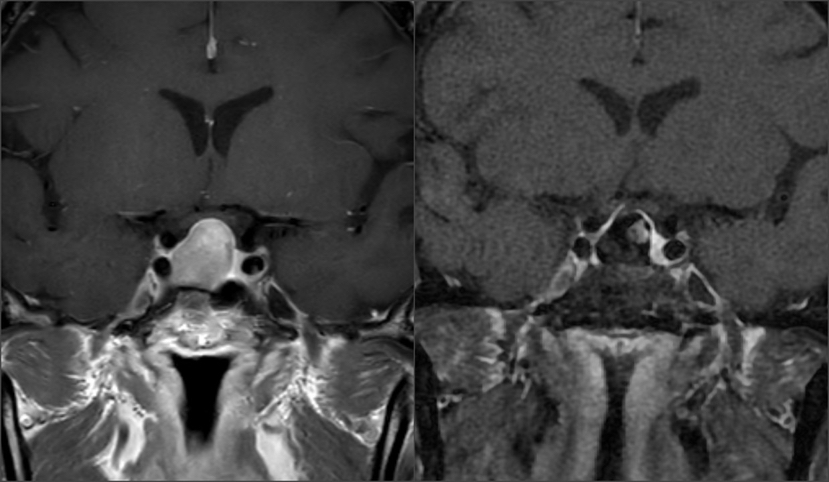

术前术后影像学对比